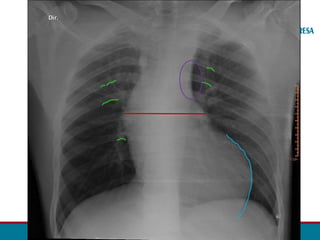

RADIOGRAFIA TORÁCICA

• Sinal de Roesler:

• Erosões bilaterais na borda inferior dos arcos costais (3ª - 9ª).

• Sinal do “ 3 invertido”

• Dilatação Subclávia E.

• Segmento estenótico aparece como um entalhe

• Dilatação pós estenótica.

• Contorno do arco aórtico apagado.